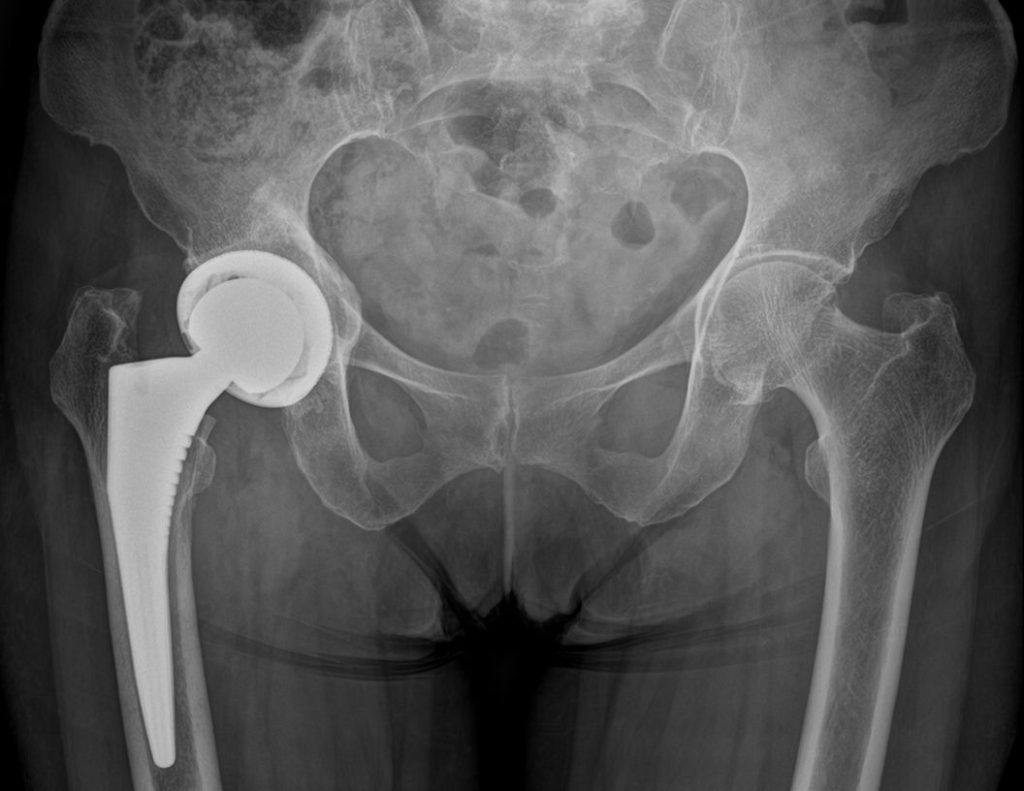

Coxartosi bilaterale

Prima

dopo